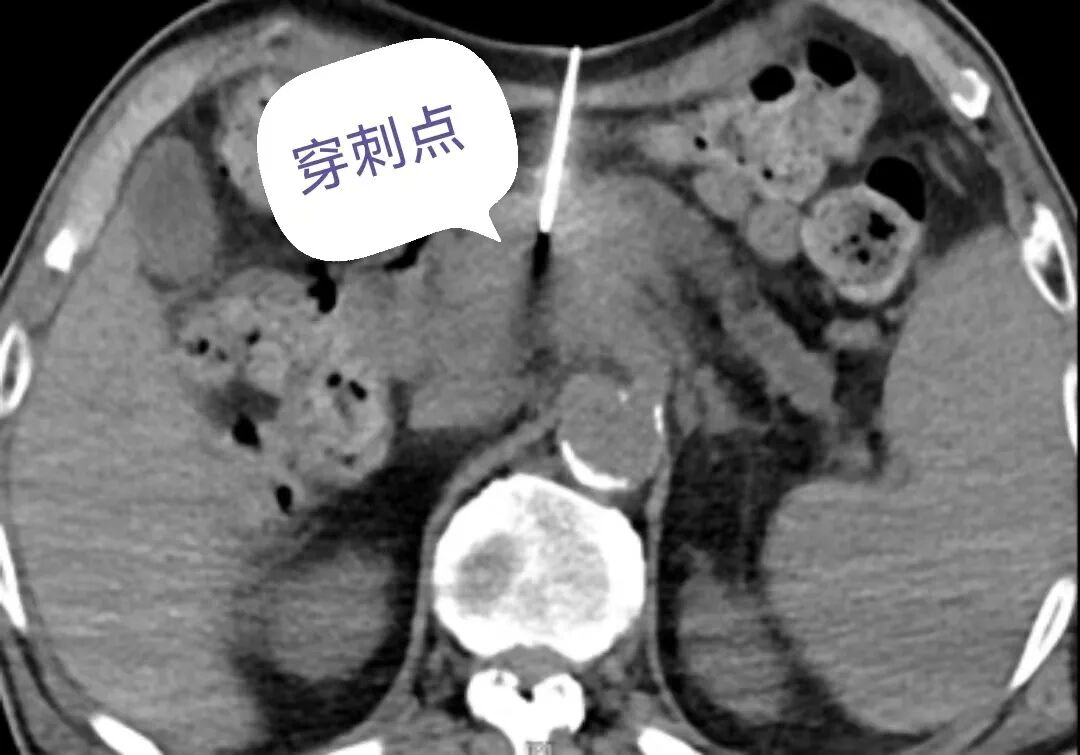

“胰腺位于人体腹部的中心,前有胃肠道覆盖,后有脊柱和肾脏阻挡,左有脾脏环绕,右有肝脏拦截,所以胰腺病变的穿刺活检极易损伤以上器官。另外,胰腺为人体中较大的腺体,血供极其丰富,胰腺头部有胰十二指肠动脉前、后弓环绕,胰腺体部和尾部有胰背动脉、胰大动脉呈梳状分支供血,这些血管纵横交错、相互交通成网,即使穿刺针到达胰腺附近,也很难避开这些血管。”丁国成解释说,该病例虽然肿块不大,但已侵及门静脉,引起静脉淤血,侧支循环形成,大量平时不开放的血管迂曲扩张,给本来就有难度的手术陡然增加了一定的困难。局麻后,在CT精确引导下,微创介入团队将套管针经皮穿刺,经多次方向调整,成功到达胰体肿块边缘,穿入活检针后精准取样,为患者顺利完成了这台高难度的穿刺活检术。